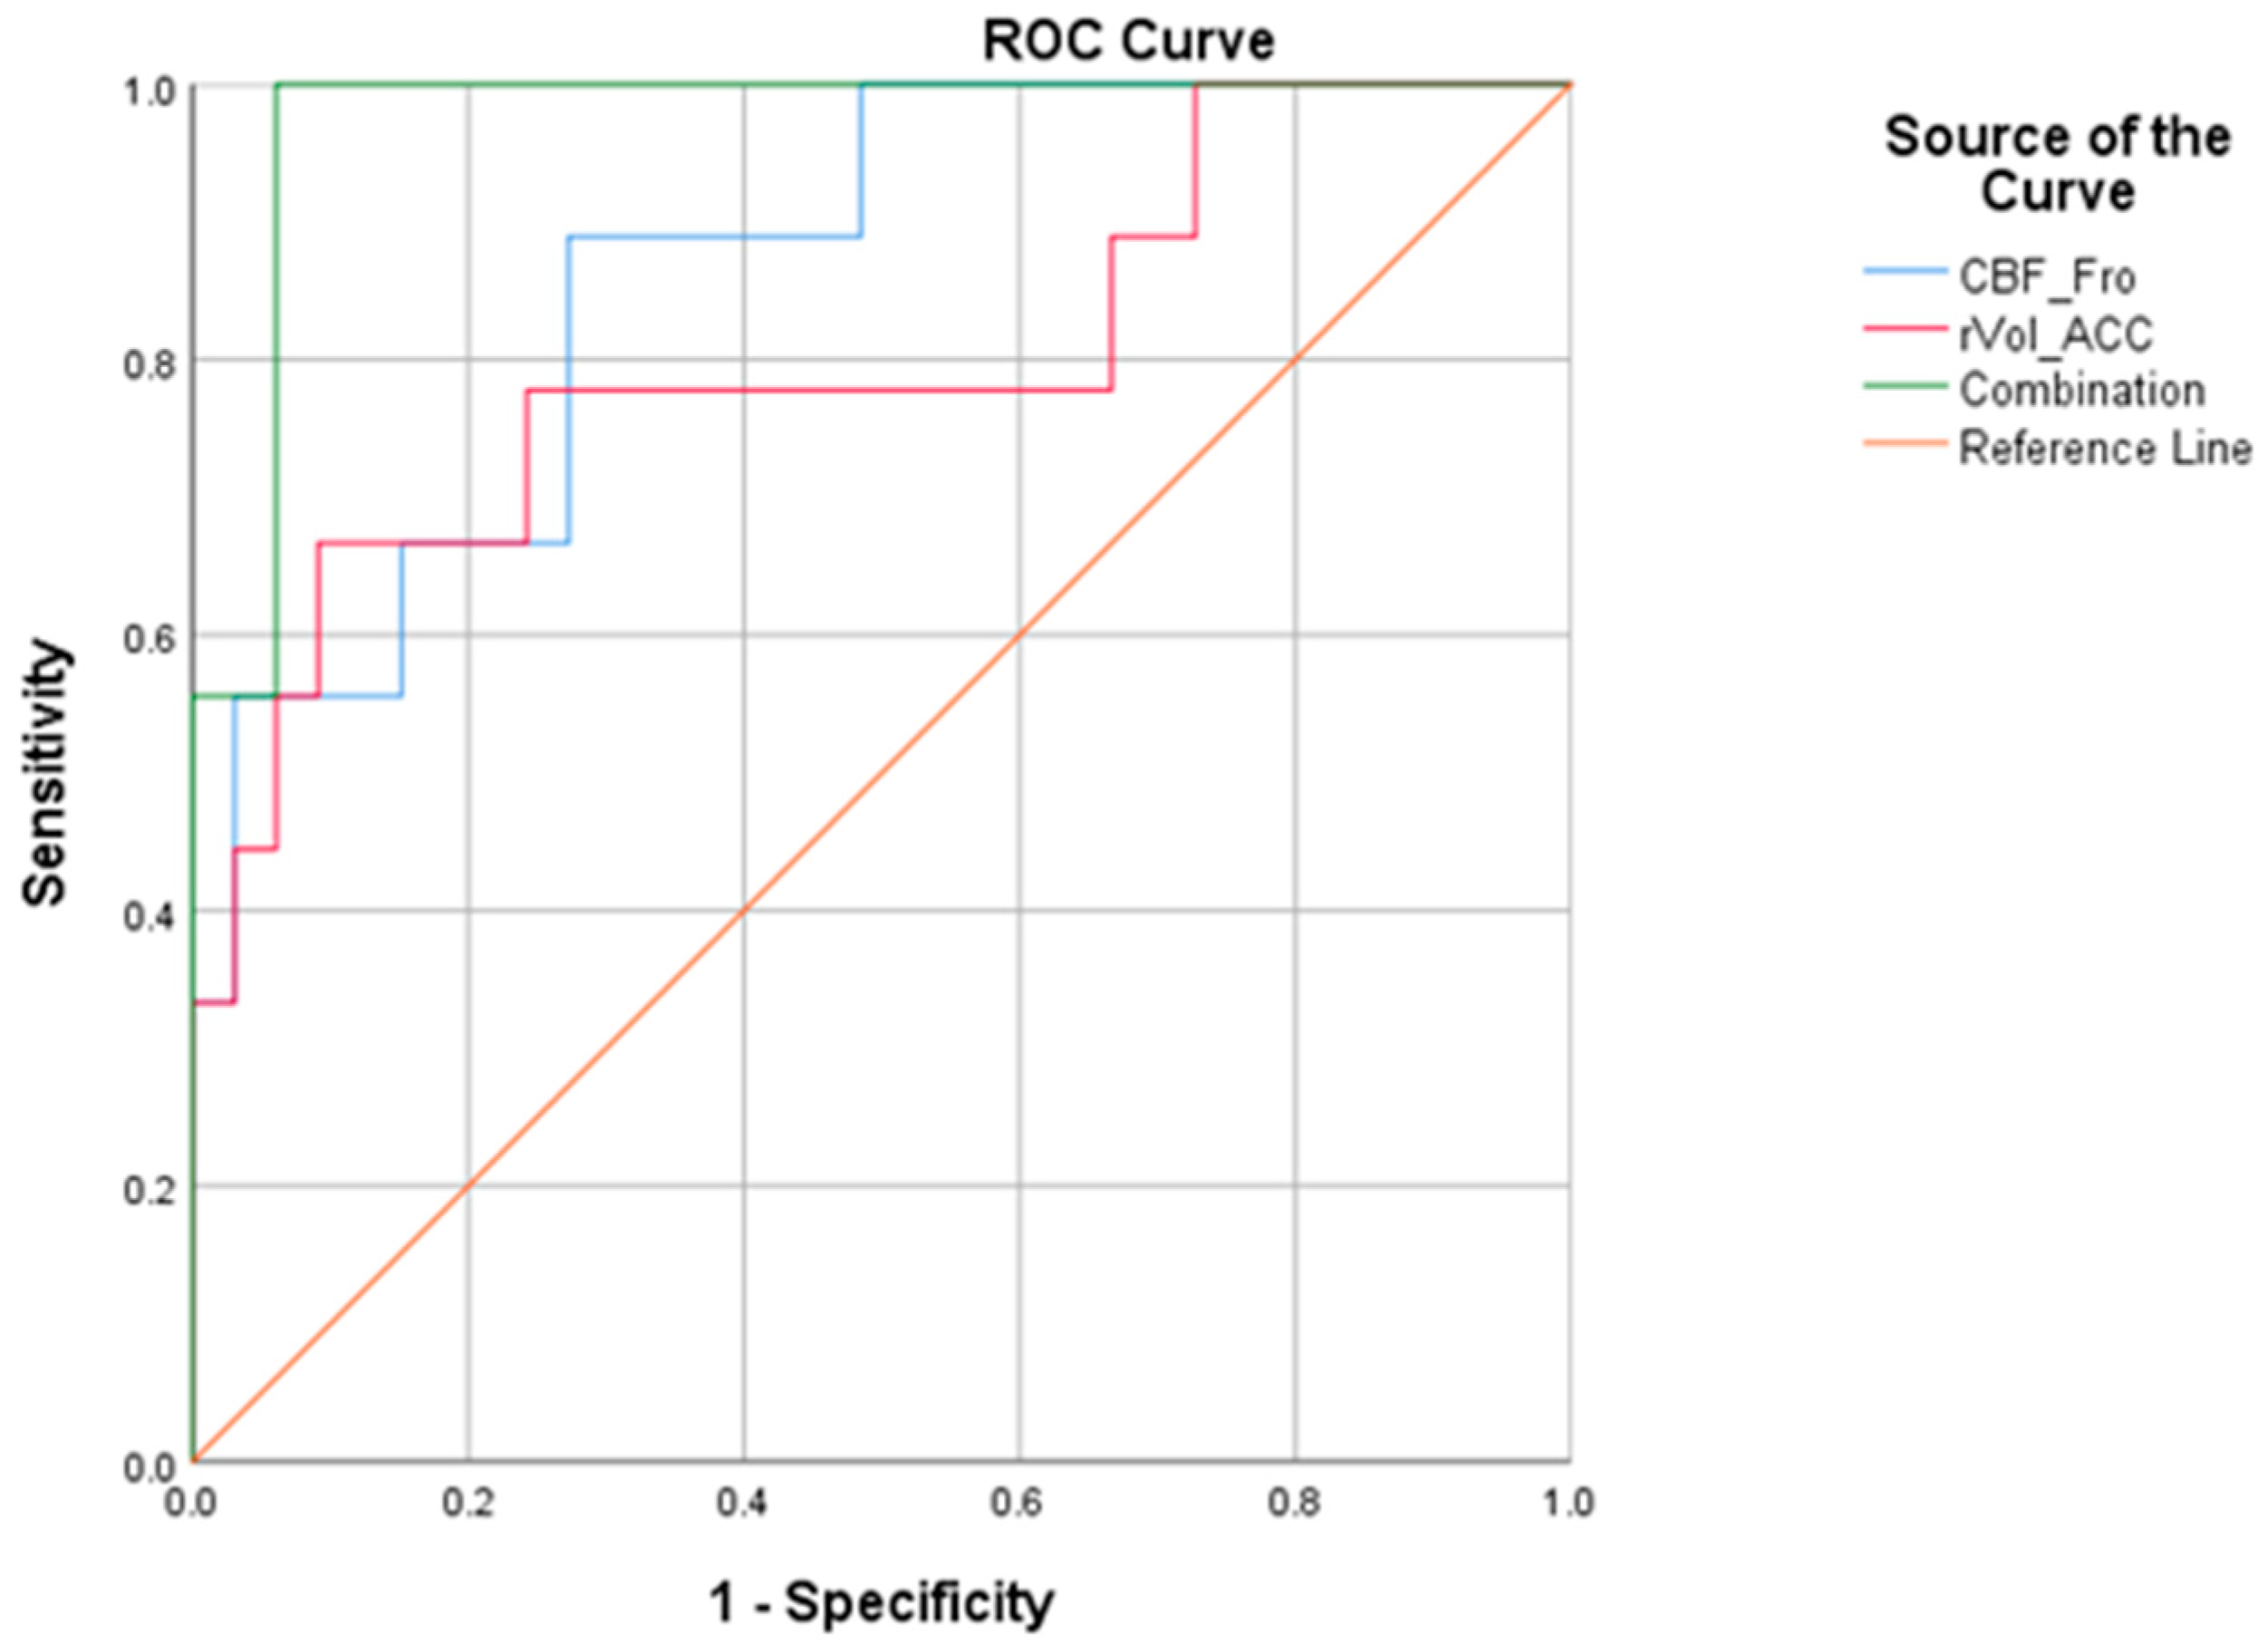

3.5. Predictive Performance of Single Parameter and Combination

| Cut-Off | Sensitivity | Specificity | Youden Index | AUC | ||

|---|---|---|---|---|---|---|

| Mean | 95%CI | |||||

| CBF_Fro | 0.17 | 0.889 | 0.727 | 0.616 | 0.862 | 0.735, 0.988 |

| rVol_ACC | 0.29 | 0.667 | 0.909 | 0.576 | 0.798 | 0.608, 0.988 |

| Combination | 0.23 | 1 | 0.939 | 0.939 | 0.973 | 0.930, 1.000 |